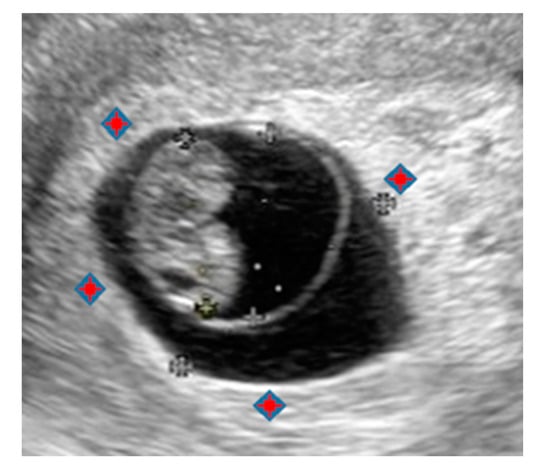

Figure 3.

Ultrasonographic image at 7 w 3 d (19.3 × 13.8 mm). The red marks show the lacunar space where AE is injected.